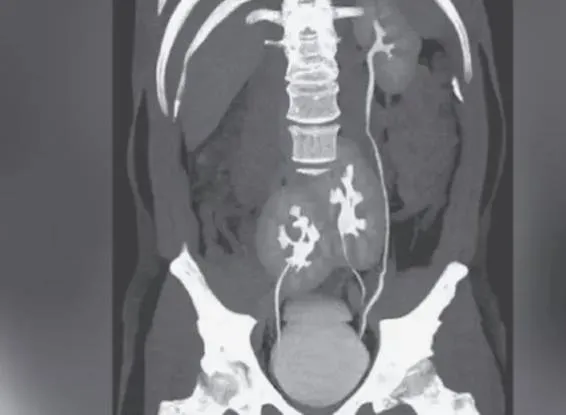

முதுகுவலி என்று மருத்துவமனைக்குச்சென்றவருக்கு மூன்று சிறுநீரகம் இருந்த சம்பவம் அதிர்ச்சியை ஏற்படுத்தியுள்ளது. பிரேசில் நாட்டைச் சேர்ந்த 38 வயதான ஒருவருக்குக் கடுமையான முதுகுவலி இருந்துள்ளது. இதனால் கடும் பாதிப்புக்குள்ளான அவர் மருத்துவமனைக்குச் சென்று மருத்துவரைப் பார்த்துள்ளார். அவரைச் சோதனை செய்த மருத்துவர் உடலை ஸ்கேன் செய்ய கூறியுள்ளார். மருத்துவர் கூறியவாறே அவரும் ஸ்கேன் எடுத்துள்ளார்.

ஸ்கேன் ரிப்போர்ட்டை எடுத்துக்கொண்டு மருத்துவரைச் சந்தித்த அவருக்கு அதிர்ச்சி காத்திருந்தது. ஸ்கேன் ரிப்போர்ட்டைப் பார்த்த மருத்துவர் இது சாதாரண முதுகுவலி தான் என்று கூறியுள்ளார். ஆனால் அடுத்து அவருக்கு அதிர்ச்சி அளிக்கும் விதமாக உங்களுக்கு மூன்று கிட்னிகள் இருப்பதாகவும், இடது புறம் ஒரு கிட்னியும், வலதுபுறம் இரண்டு கிட்னியும் இருப்பதாகவும் அவரிடம் கூறியுள்ளார். இதனால் அதிரச்சி அடைந்த அவர், அதனால் ஏதேனும் உடலில் பாதிப்பு ஏற்படுமா என்று கேட்டுள்ளார். ஆனால், அப்படி எந்த பாதிப்பும் ஏற்படாது என்றும் உலகில் சிலருக்கும் மூன்று கிட்னிகள் இருப்பதாகவும், இதனால் பயப்பட வேண்டாம் என்றும் அவர் தெரிவித்துள்ளார்.